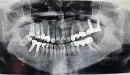

Здравствуйте! У меня было неудачное протезирование в 1913 году. Долго искала хорошего врача. Он удалил часть зубов и предложил поставить импланты: внизу справа два (6-й и 7-ой) и в верху слева два(7-й и 8-й). После установки коронки верхних имплантов проходят как бы над языком. Врач сказал, что это моя особенность, но через некоторое время (подтачивая зубы по высоте то с одной стороны, то с другой несколько раз) согласился, что не хватает теперь 8-ки в низу слева. Мне очень неудобно, так как язык западает и натирается, и высота прикуса уменьшилась, языку стало мало места и он травмируется по бокам о зубы и натирается сверху и сбоку с двух сторон. Импланты были установлены 20 ноября, последнюю коррекцию врач сделал за 1,5 недели до Нового года и теперь устаю даже говорить. Первоначально я договаривалась, что мосты в верху надо менять, но он сказал, что стоят и пусть стоят. Под левым мостом в верху у меня стали частые воспаления в виде гнойничков и боли. Мост врач снял 28 января, но сломал зуб (это 6-ка, но на этом месте была 5-ка), на уровне десны и штифт сломался. Врач сказал, что или сделает металлическую вкладку или удалит корень и поставит импланты. Что лучше? Устоит ли мост на вкладке? Можно ли увеличить высоту прикуса и как? Врач сказал, что теперь увеличить высоту прикуса нельзя, так как другие зубы не будут контактировать. До этих многократных коррекций высоты зубов языку хватало места, он не натирался и не зажимался... Врач челюстно-лицевой хирург всё делает сам, репутация хорошая, но мне что-то не очень везёт... Заранее огромное Вам спасибо! С уважением к Вам Ольга.

Прикрепленые фото

Добрый день, уважаемая Ольга. Лично я не понимаю, для чего нужно было устанавливать имплантаты на место восьмого зуба. На мой взгляд, это полная неграмотность. Также, протезирование на имплантатах, на мой взгляд, некорректное и нерациональное.

Да и лечение каналов и коронки оставляют желать лучшего.

Что касается подтачивания и коррекции коронок по прикусу в полости рта, это говорит о крайней непрофессиональности. Рекомендую, не продолжать никаких действий, так как, судя по увиденному, ничего хорошего вам не светит. Приезжайте к нам, я вас посмотрю, и все вам расскажу, в письме сложно разъяснить вам рациональный план лечения.